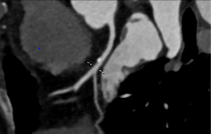

CT有平扫、增强扫描、CT造影3种不同的检查方式。其中,CT平扫常被用于常规检查;而增强扫描则是在平扫的基础上,在静脉中注入造影剂,使病变能更清晰地显示出来;CT造影则是静脉中注入造影剂(剂量和注射速度高于增强扫描)以显示一些特殊结构,如心脏冠状动脉造影就是用来显示心脏冠状动脉结构的。

CT冠脉造影